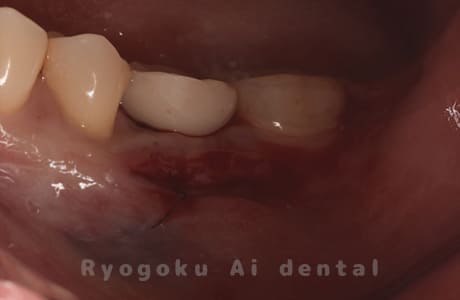

Case08

-

- 原因

- 左下7番歯根破折

- 治療内容

- インプラント治療

- 治療費用

- 約600,000円

左下の腫れが治らないとの事でご来院された患者様です。歯が割れていたため、抜歯を行い、骨に代わるお薬を入れ、インプラントを埋入致しました。経過良好で大変満足していただけました。

<リスク・副作用>

治療後、痛みや違和感、出血、腫れなどが出る事があります。喫煙者、糖尿病などの方の場合、歯が生着しない場合があります。